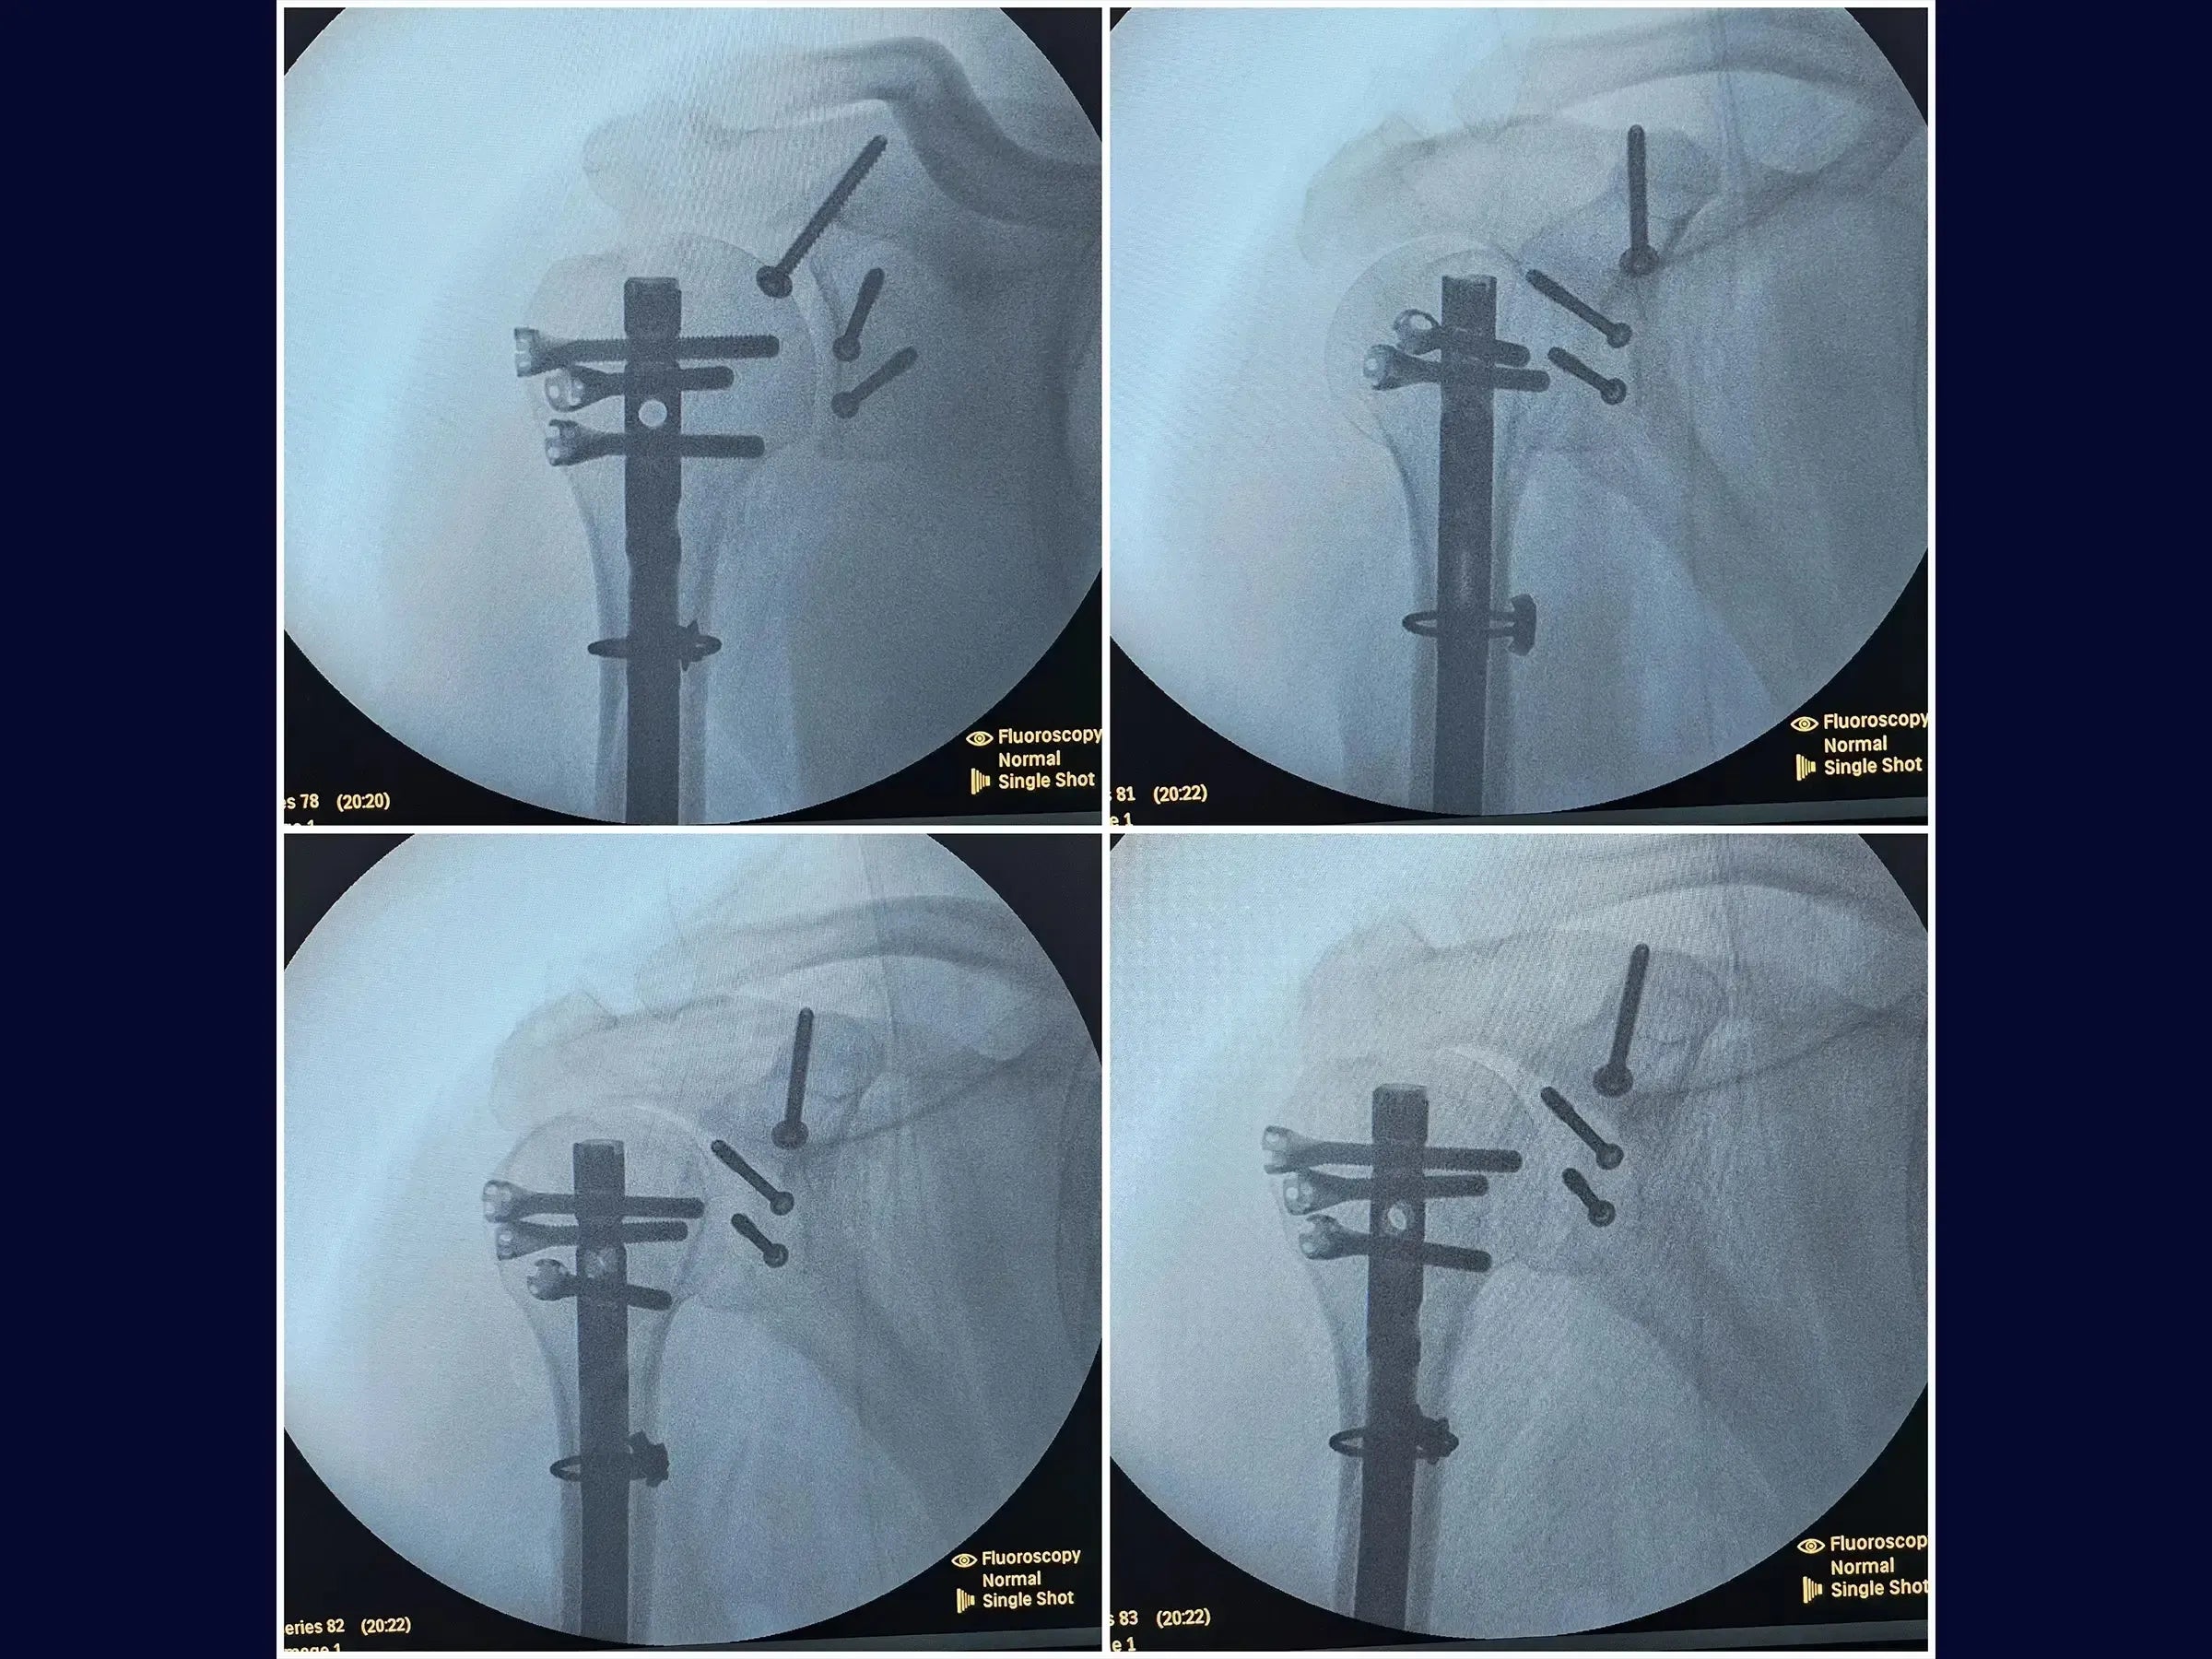

- Osteossíntese com haste intramedular e cerclagem no úmero.

- Fixação com parafusos na glenoide e coracoide.

- Reconstrução Segmentar do Úmero: Abordagem sistemática para identificação dos vértices da fratura, redução do segmento proximal e fixação com haste intramedular e parafusos proximais, complementada por cerclagem, para estabilidade e restauração anatômica.

- Fixação Precisa da Glenoide: Técnica de incisão e separação do subescapular da cápsula articular para exposição e redução do fragmento da glenoide, com inserção de fios guia e parafusos para assegurar a congruência articular e estabilidade.

- Estabilização do Coracoide: Demonstração da fixação do processo coracoide, preso ao tendão conjunto, com parafuso de compressão.